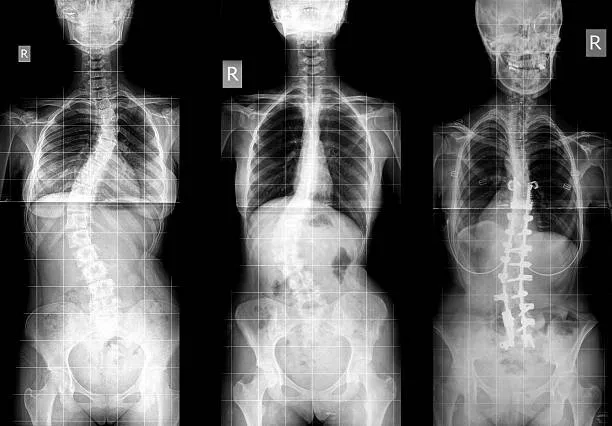

An X-ray showing the curve of adult scoliosis